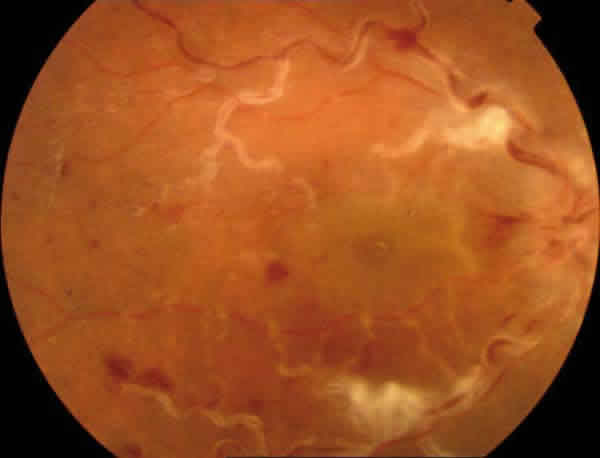

Varón de 21 años que acude a urgencias por visión borrosa intermitente de unos 20 seg. de duración en ojo derecho (OD) desde hace 15 días, con sensación de nube constante los últimos 5 días. Es fumador de 20 cigarrillos al día y está en tratamiento con doxiciclina para el acné. En la exploración oftalmológica la agudeza visual (AV) era de 0.150 en OD y de la unidad en el ojo izquierdo (OI) sin DPAR en ninguno de ellos. En la biomicroscopía anterior (BMA) se observaban células de intensidad ++ en OD y de + en OI con precipitados endoteliales finos y escasos en ambos ojos (AO). La tensión ocular era de 10 en AO. En el fondo de ojo (FO) existía un edema de papila bilateral con congestión y tortuosidad vascular más llamativa en el OD con alguna hemorragia y exudados (fig. 1). En la angiofluoresceingrafía (AFG) aparecía una hiperfluorescencia en ambas papilas y en grandes venas del OD y en la angiografía con verde indocianina (ICG) no se observaban focos de coriorretinitis (figs. 2 y 3). El test de colores era normal en AO y el TAC cerebral sin hallazgos. Se instaura tratamiento tópico con corticoides, antibióticos y midriáticos y a los 2 días la AV baja en OD a 0.05 observándose un importante edema macular (fig. 4). El estudio complementario con Rx de Tórax, analítica para descartar patología infecciosa (Borrelia, Bartonella, Treponema P, etc.) e inmunitaria con batería completa de uveitis así como Ac Antifosfolípidos y pruebas de coagulación, glucemia, lípidos etc., fue negativo excepto la elevación del ASLO y el HLA B5 +. El estudio neurológico descartó un «pseudotumor cerebri» que pudiera estar en relación con la toma de tetraciclinas. La RMN craneal descarta asimismo la trombosis de los senos venosos y la existencia de enfermedades desmielinizantes.

Fig. 1. Retinografías de AO al inicio del cuadro, observándose un edema de papila bilateral con mayor afectación vascular en el OD.